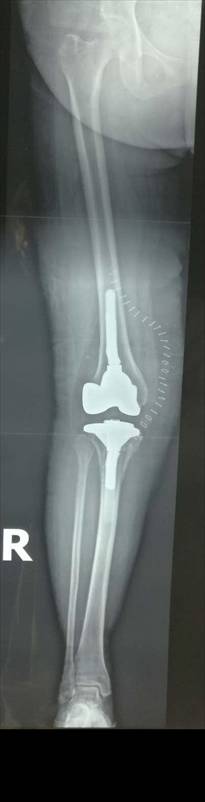

全膝表面置换术治疗重度骨关节病

优点:疗效可靠,膝关节病的最终解决方案。

术前术后对比

全膝关节翻修术